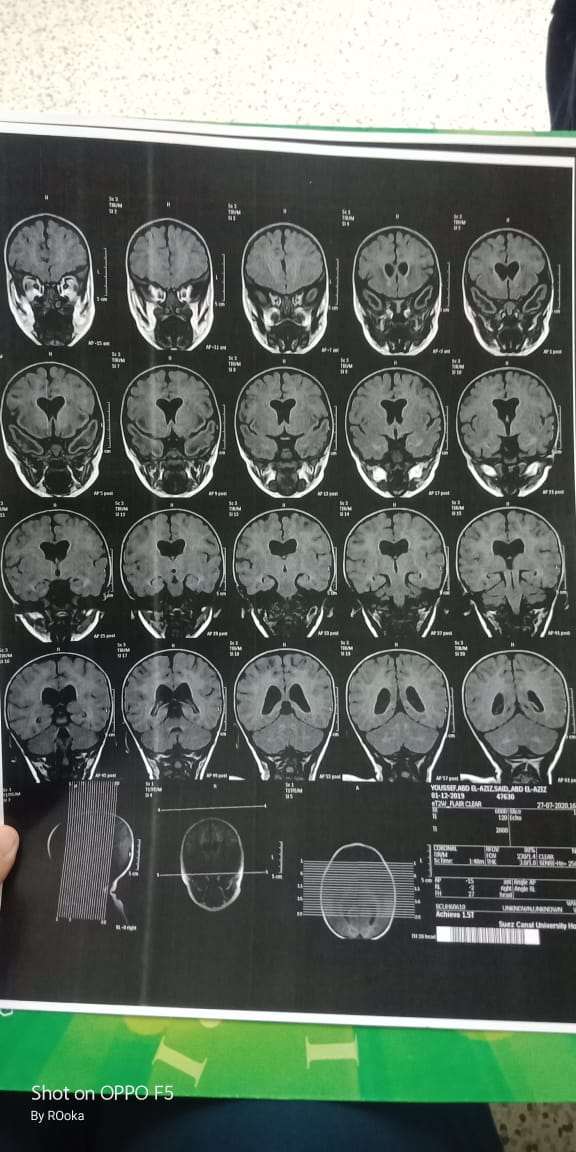

وأضاف عبد العزيز، في تصريحات خاصة لـ القاهرة 24: اكتشفنا مرض يوسف وهو عنده 6 شهور، طلع عنده نقص في المادة البيضاء، ونقص في الأكسجين، مع تآكل في القشرة المخية.

وأكد أن طفله فاقد للحركة والكلام حاليًا، مع تمدد حجم الدماغ، نتيجة معاناته من اختلالات عصبية، التي تنشأ عن المرض، معقبًا: الطفل يحتاج لجهاز طبي يساعد على تخفيف حدة الأعراض، وفقًا لاستشارة الأطباء.